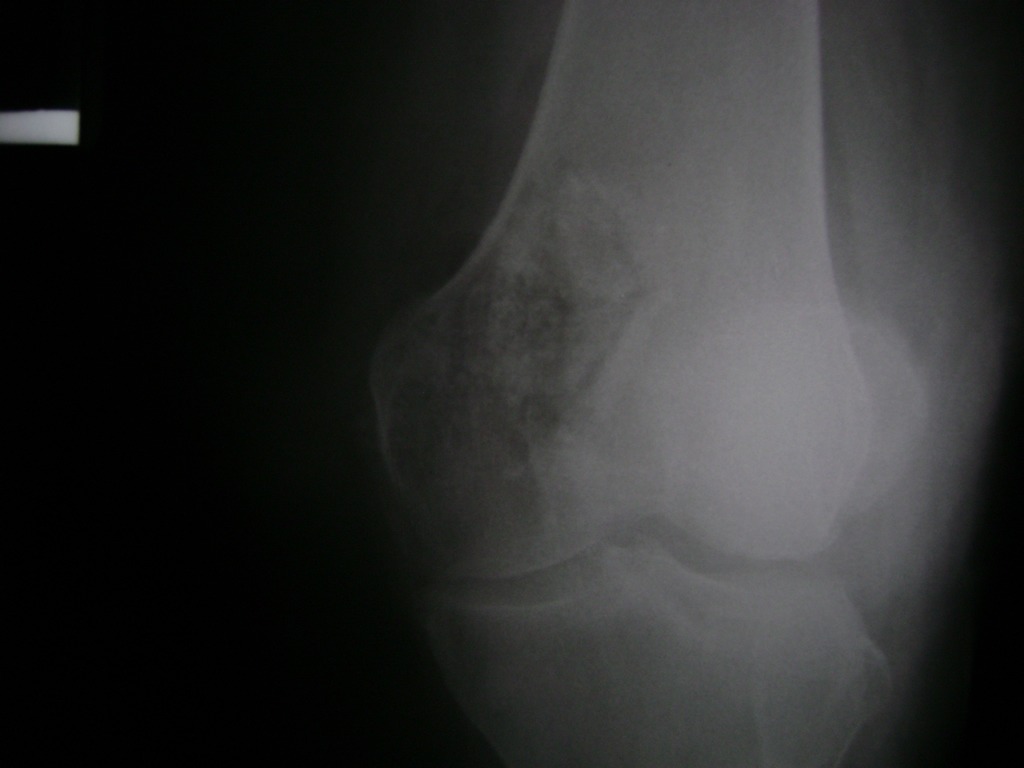

Cirugía de Fémur - Rodilla